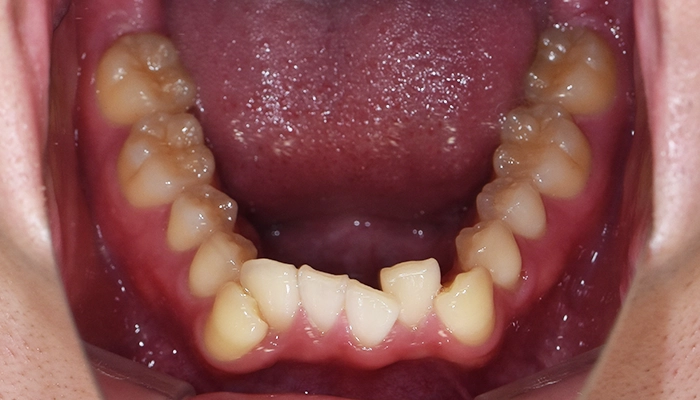

当院にてカウンセリング・検査後、上左右2本、左下1本の計3本と診断させていただき、マウスピース型矯正装置(インビザライン)での治療をご提案しました。

顎が小さい場合に無理にすべての歯を並べてしまうと、歯がぎゅうぎゅう詰めになりかえって逆効果です。インビライン

今回の治療では上の両側4番目の歯と、左下の4番目の歯の計3本を抜歯しました。

ワイヤーだと片側抜歯を行うと正中のラインが抜歯した方向へ流れてしまうことがありますが、今回はマウスピース型矯正装置(インビザライン)で行ったため、そのような反作用は生じませんでした。